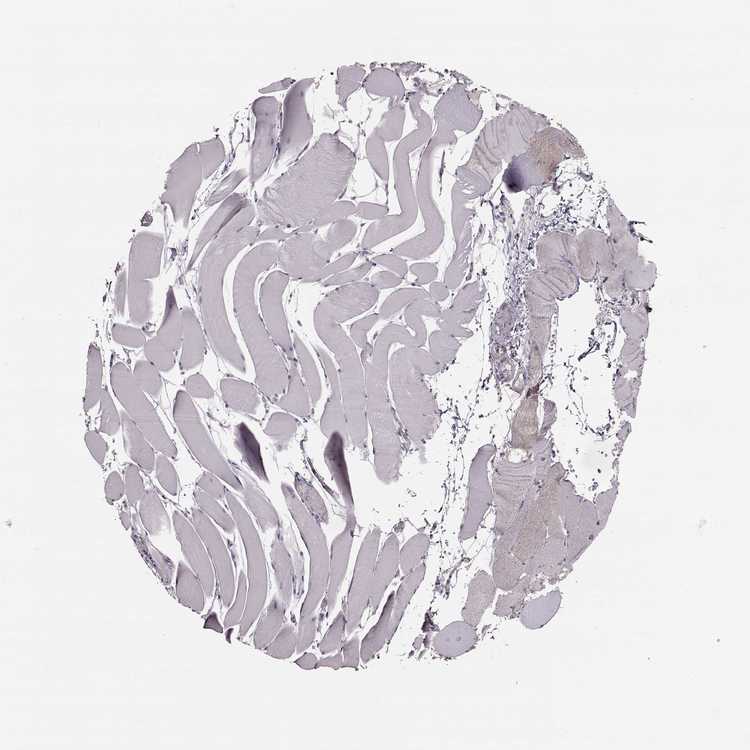

TISSUE PRIMARY DATA SKELETAL MUSCLE Show tissue menu

SKELETAL MUSCLE - Antibody stainingi

Antibody staining in the annotated cell types in the current human tissue is reported as not detected, low, medium, or high, based on conventional immunohistochemistry profiling in selected tissues. This score is based on the combination of the staining intensity and fraction of stained cells.

Each image is clickable and will lead to virtual microscopy that enables deeper exploration of all samples and also displays staining intensity scores, fraction scores and subcellular localization as well as patient and tissue information for each sample.